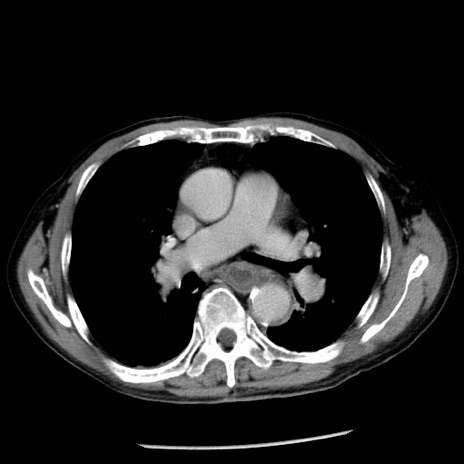

症例26(横断像)

【症例】80歳代男性

【主訴】嘔吐

【現病歴】昨晩2回嘔吐あり、今朝になっても嘔吐あり。来院。

【既往歴】胃潰瘍

【身体所見】意識清明、BT 37.6℃、BP 166/95mmHg、HR 100bpm、SpO2 97%、腹部:平坦・軟、腸蠕動音聴取良好、圧痛なし。

【データ】WBC 21900、CRP 1.46